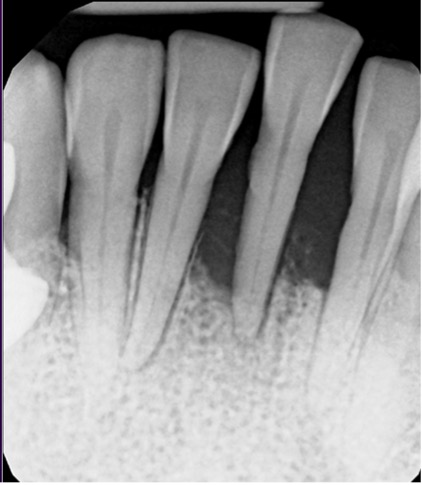

Radiographs showed severe bone loss. At first glance, this looked like a tooth destined for extraction.

When we probed the rest of the mouth, we found deep pockets elsewhere—like a 9 mm pocket on the distal of tooth #4—with surprisingly little calculus.

This was aggressive periodontal disease, where the probe drops apically with almost no resistance and minimal calculus is present.